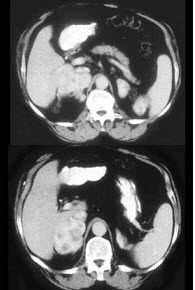

女,32岁,阵发性高血压2年余,请结合所提供图像,作出诊断( )

A:左肾上腺腺瘤

B:左肾上腺腺癌

C:左肾上腺转移瘤

D:左肾上腺嗜铬细胞瘤

E:左肾上腺淋巴瘤